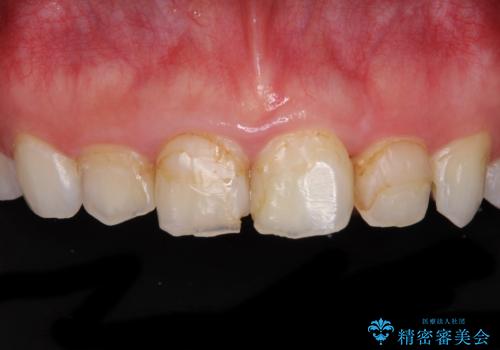

矯正治療前に前歯のむし歯治療を行ったものの、樹脂で充填するには虫歯が広範囲であったため、審美的に問題がありました。

矯正治療にて歯並びを整えた後に、虫歯の大きかった5本の歯をセラミッククラウンにて補綴し、明るい口元になりました。